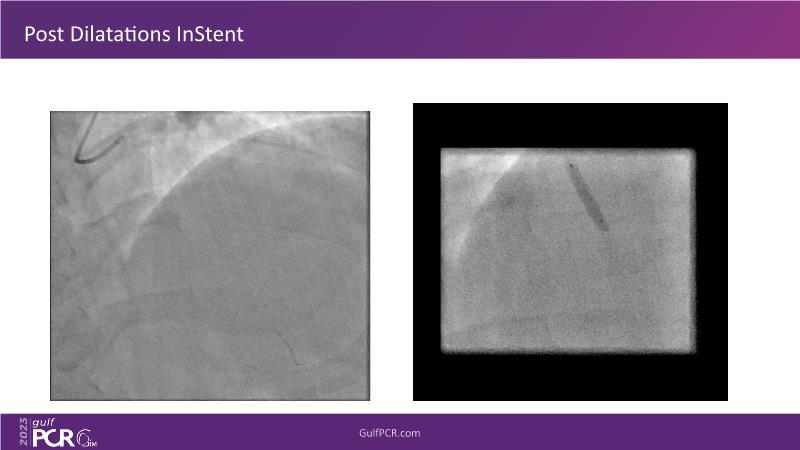

- To understand novel tools and techniques for effective management of bifurcation lesions and long diffused lesions using dedicated stenting solutions